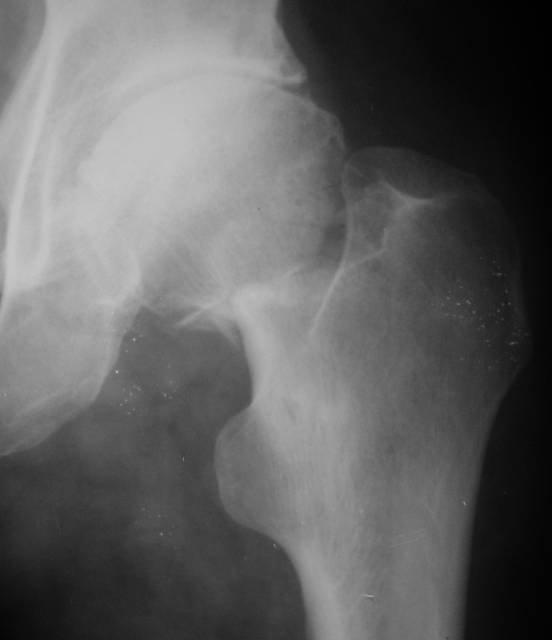

AV> опираясь на стул. На ногу не наступает. Укорочение 8 см. Иногда

А за счет чего такое укорочение? По снимку не видно соответствующего дефекта. Ну плюс приводящая контрактура - но все равно как-то уж больно много. Может, сделать снимки и таза обзорный с обоими проксимальными отделами бедра, и коенный суставов с приложенной линейкой какой?

Судя по снимку, максимум истинное укорочение около 4 см, что может быть коррегировано интраоперационно. Вопрос в другом: куда ставить ацетабулярный компонент в истинную или во вновь сформированную ( впадина диспластичная).

Терзают смутные сомнения, что у больного и до перелома нога уже была короче: порасспрашивайте анамнез поподробнее.

По рентгенограммам укорочение не более 4 см, остальное возможно за счет контрактуры. Опыта с низведением аппаратом Илизарова нет, но мы одномоментно такие укорочения корригировали вполне успешно (в год 5-10 именно таких и проходит). Лишние этапы пожалуй только будут способствовать инфекции. Доступ чаше применяем передне-наружный, а вот протез наверное поставили бы здесь на цементе - остеопороз выражен.